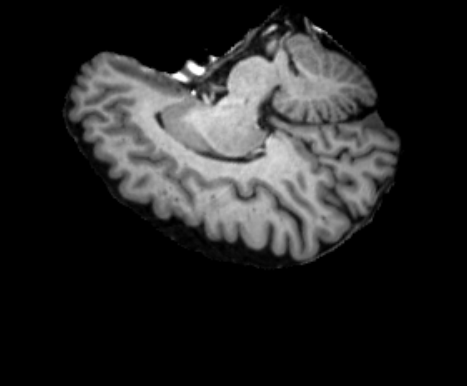

3.2.2 Robustness

In this experiment, we evaluate the robustness of Polaffini and the competing methods by computing a failure rate. We considered as potential outliers all cases for which the average Dice score over all regions after registration was below 0.34 (Z-score below -1.5, pooling Dices from all affine methods). All potential outliers were visually inspected to assess the reason behind the poor anatomical structure overlap score. All of them were clear failure cases, not just a residual misalignment to be expected after an affine registration. The failure counts for each method are reported in table 2. Almost all of the failure cases only occurred when registering with Flirt, mostly when subjects from the IXI dataset were involved. The most common failure type, showcased in Fig 6-a., consists of a local minimum where the frontal part of the moving brain is matched with the cerebellum of the reference one, a less frequent upside-down outcome is showcased in Fig 6-b. We suspect it is due to the fact that images from IXI have their axes ordered differently compared to the other two datasets and the template. However, since this information is contained in the header, it is unclear why Flirt could not handle the situation properly. Without the restriction of the angle search to , Flirt would give worse results (19 failure cases for subject-to-template and 61 for subject-to-subject). The only failure case using Anima for subject-to-subject is shown in Fig 6-c. For the rest of this section, we discard registrations if at least one of the methods has failed.

| reference | moving | moved | reference and moved | |

| a. | ukb_1154012-20252 | adni_AD-012-S-0720 | registered with Flirt | |

![]() |

|

| b. | ixi_165-HH-1589 | ukb_1145033-20252 | registered with Flirt | |

| c. | ixi_143-Guys-0785 | adni_MCI-003-S-6258 | registered with Anima-aff | |